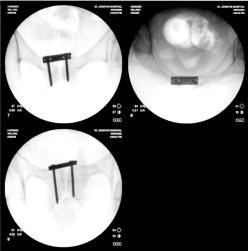

Screw Removed from Right Ankle

As can be noted in many of the right ankle x-rays, there was a screw that Dr. Keller placed in Liam’s lower right fibula which was

supposed to be through the plate in the fibula, but instead Dr. Keller missed the plate and simply screwed it into the bone. In the

position that the screw was place it caused considerable pain for Liam and obstructed Liam’s normal foot motion. The images below

show Dr. Gottlieb correcting Dr. Keller’s mistake.